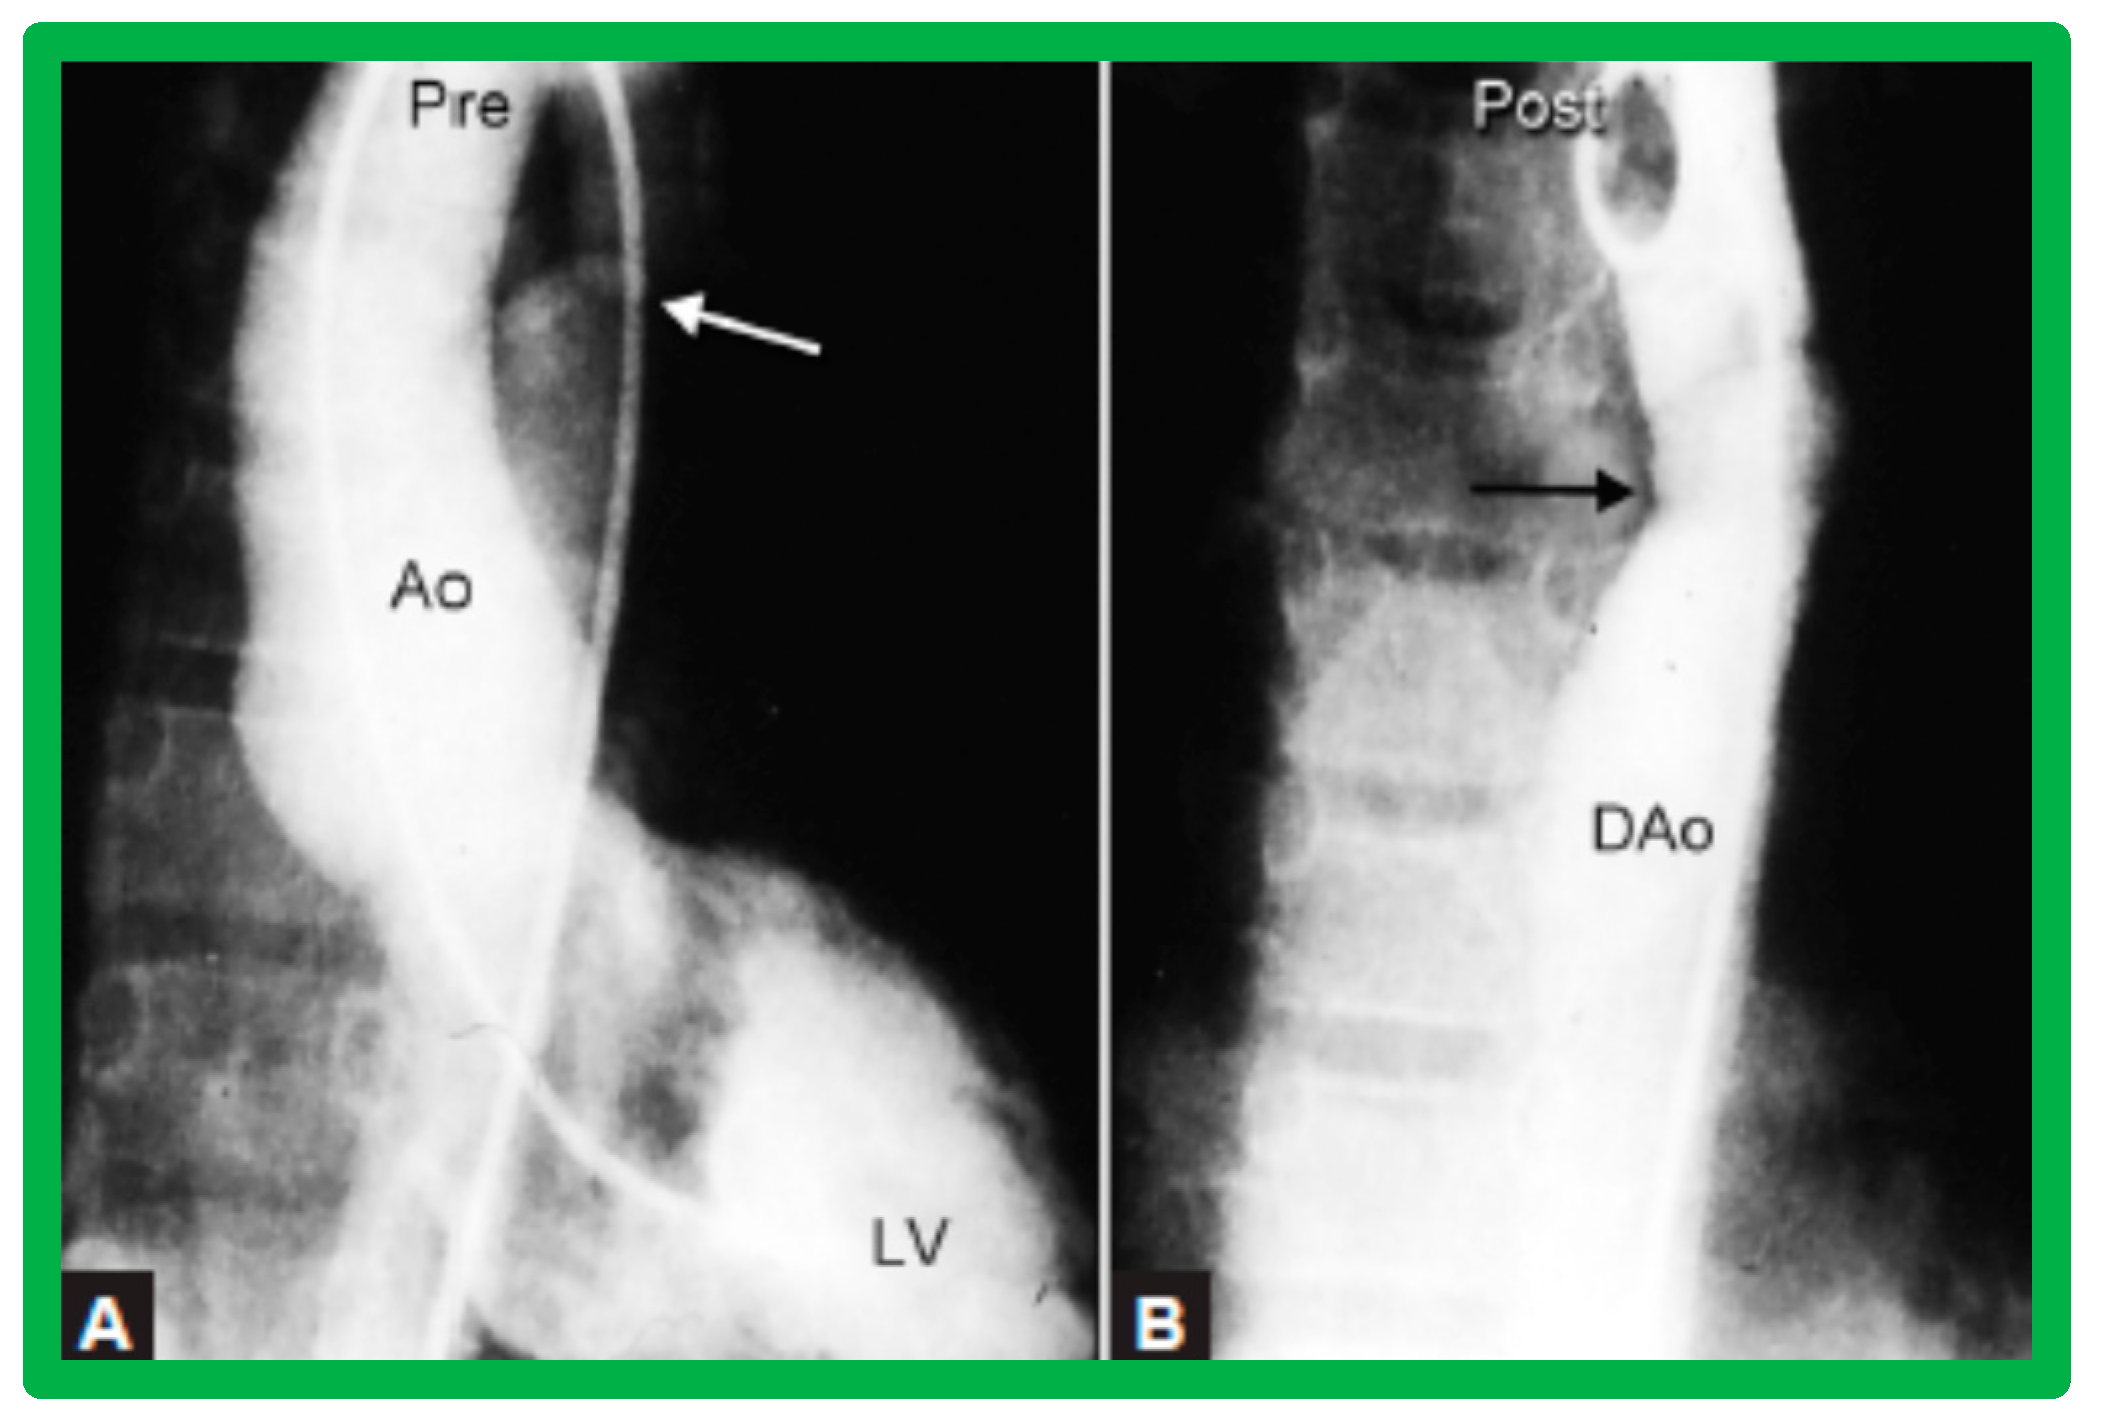

4.3. Aortic Coarctation–Native

Revisit BA in the Neonate and Young Infant